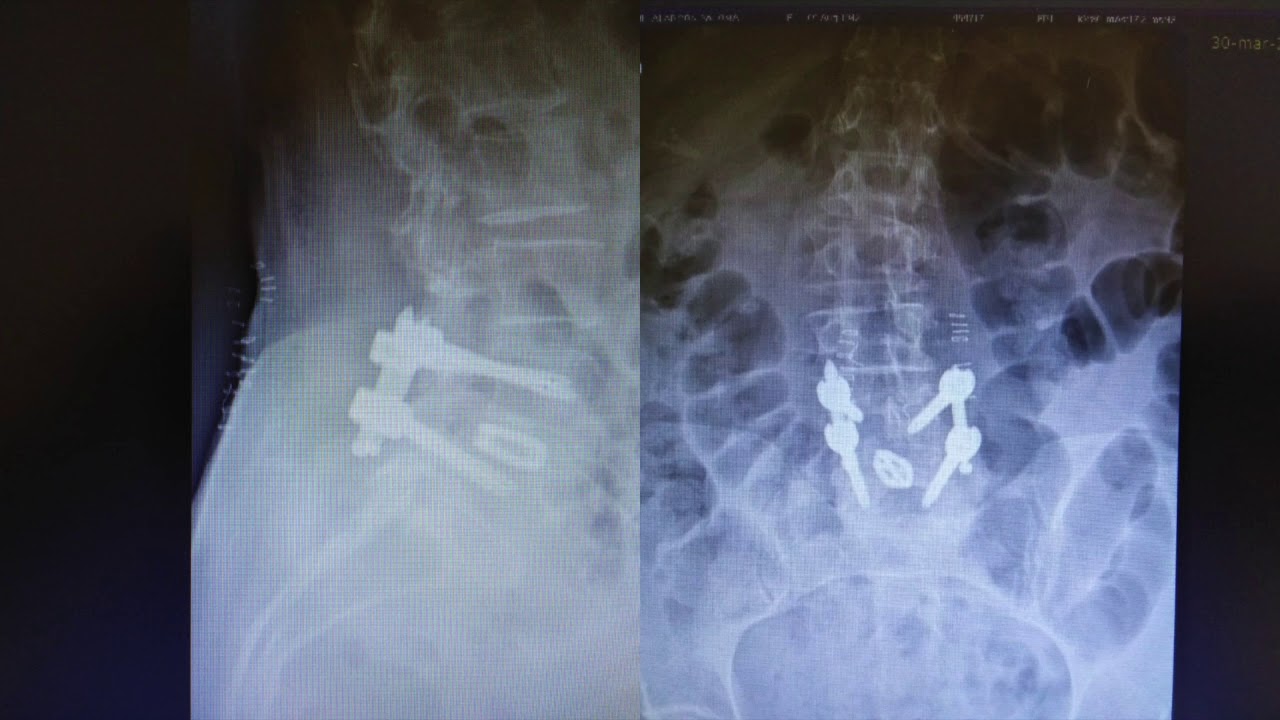

Cirugía espinal mínimamente invasiva

La cirugía percutanea minimamente invasiva en columna esta demostrado que es un procedimiento efectivo y seguro. Reduce el dolor postquirúrgico, reduce la posibilidad de transfusión por la poca perdida de sangre, minimiza el riesgo de infección al ser una cirugía cerrada y sobre todo la recuperación del paciente es mucho mas rápida, logrando ponerse de pie y empezar a andar enseguida y tambien disminuye el ingreso hospitalario. Ademas al no lesionar la musculatura disminuye la posibilidad de inestabilidad del segmento superior o inferior tras la cirugía.